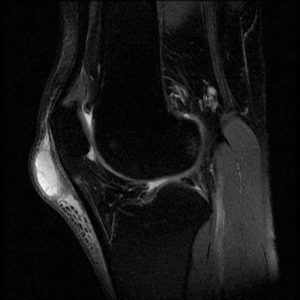

Figure 2 is a fat suppressed sagittal image of a normal knee. The patellar ligament appears as the low signal intensity structure (black) joining the inferior pole of the patellar to the tibial tubercle. The subcutaneous soft tissue anterior to this ligament is of rather uniform thickness and displays largely low to intermediate signal intensity.